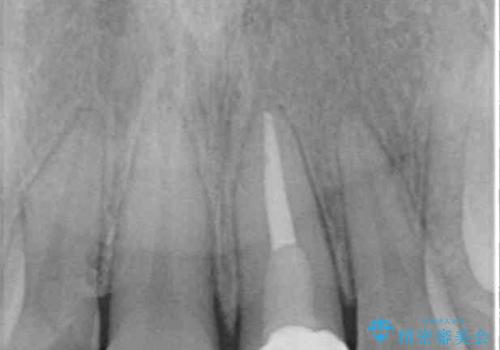

- 前歯の歯並びと不自然な色をした前歯のクラウンを気にして来院された患者様です。

上下前歯の歯列不正はインビザラインにより歯列を整え、その後に、前歯をオーダーメイドタイプのオールセラミッククラウンにて補綴治療することとしました。

初診時には、歯並びを整えることのみを検討されていましたが、歯列が整うにつれて不自然な色合いが気になるようになり、矯正治療を行ってから補綴治療をする計画を受け入れてくださいました。

口元の印象が明るく変わり、患者様には大変満足していただきました。